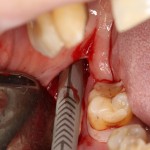

Через три месяца результат:

можно ставить формирователи и заканчивать лечение: